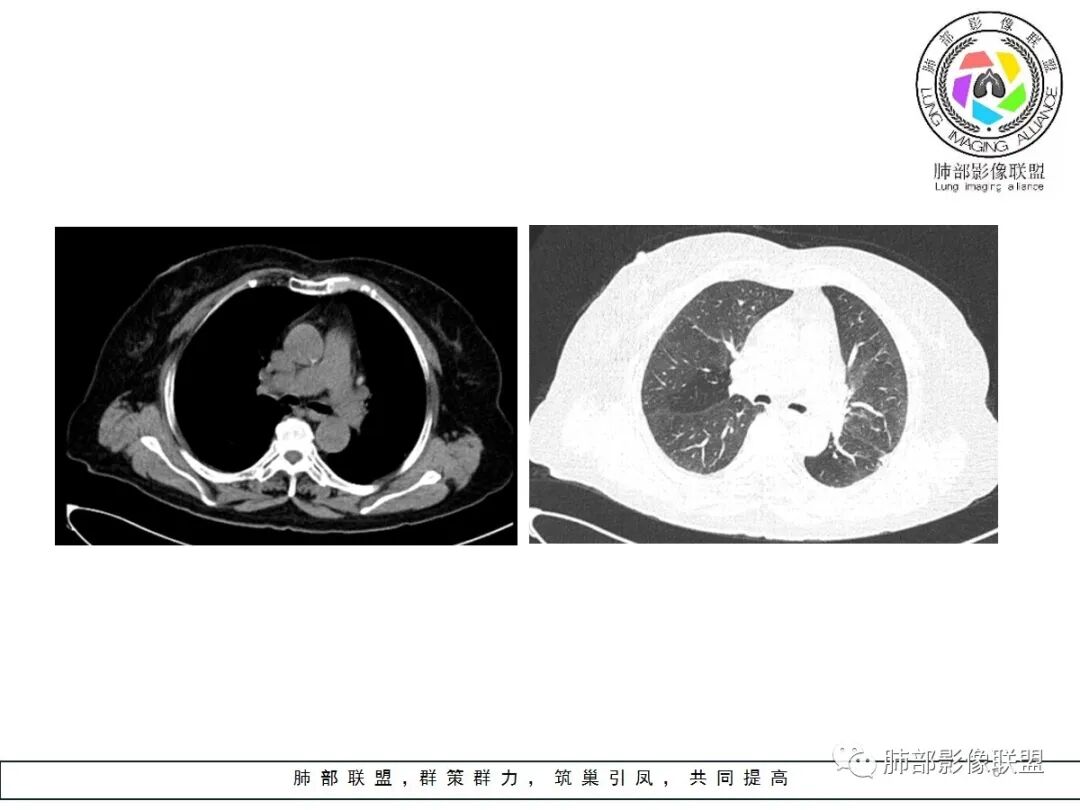

一、本例恶性征象较有特征的是脐凹征。

1.脐凹征:分叶状结节局部凹陷的部位受到血管阻力而形成,表现为血管进入分叶之间,脐凹相对比较对称光滑,近肺门侧多见,与血管走行方向一致。

2.95%见于恶性肿瘤,5%为炎性病变。

3.病灶显著强化不支持结核;边界清楚,肺门一侧波浪状改变,患者为老年女性,缺乏临床表现,尽管影像有一些炎性灶特点,但恶性肿瘤性病变不能除外。